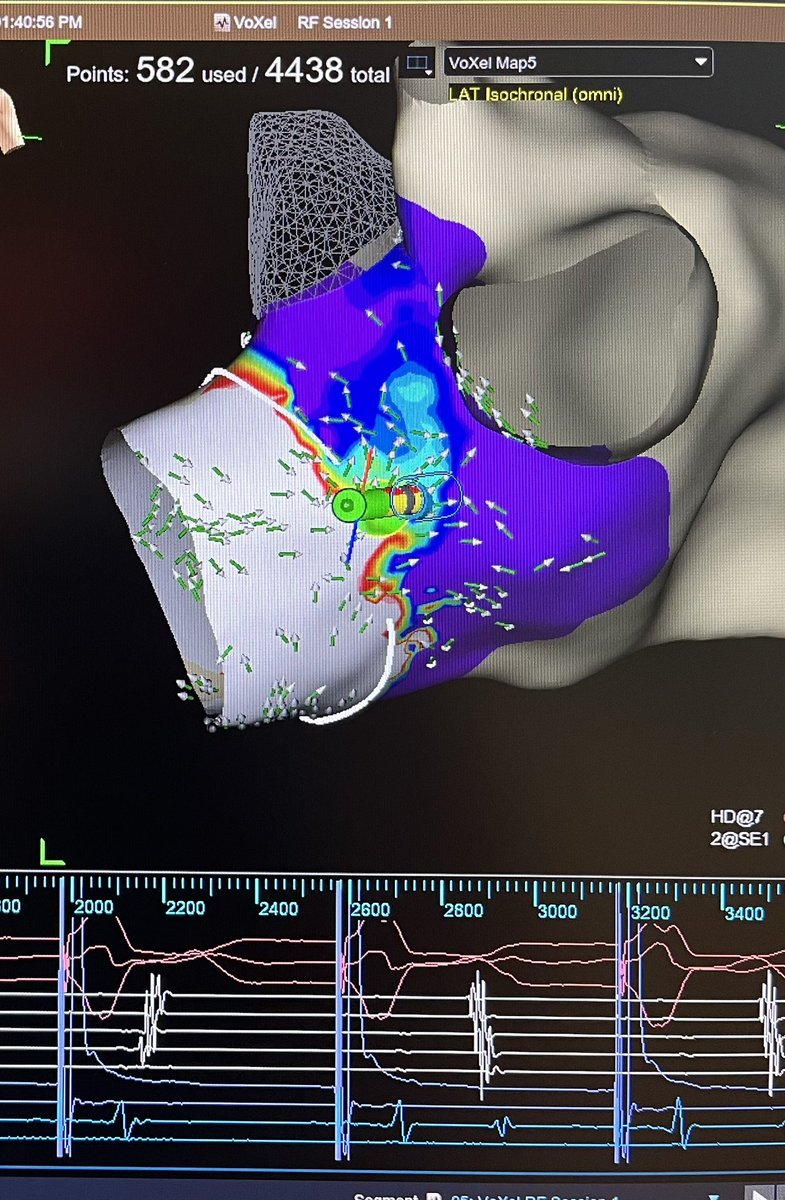

VT storm ablated with a first burn term over the weekend thanks to @JRWinterfield. #GridX with OT near field algorithm allowed for quick and accurate mapping in complex substrate.